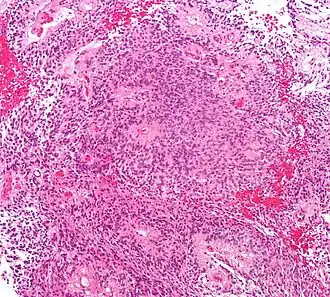

Astrocitomas

Vários sistemas de categorias foram propostos na literatura ao longo do tempo para classificar a malignidade dos astrocitomas. Desde 1993, o sistema de classificação de quatro níveis proposto pela Organização Mundial da Saúde (WHO) tem sido o mais utilizado e aplicado. Baseia-se em quatro características histológicas: aumento da densidade celular, mitose, proliferação endotelial e necrose. Posteriormente, astrocitomas de grau I, como astrocitomas pilocíticos, são tipicamente de histologia benigna. Astrocitomas II. Os graus (difusos) mostram o aumento da densidade celular como única característica histológica e são neoplasias com menor grau de infiltração. Astrocitomas III mostram uma mitose significativa. grau (anaplástico). E proliferação endotelial ou necrose são vistas em astrocitomas IV. graus, os chamados glioblastomas.

Astrocitoma anaplásico

Astrocitoma anaplásico é um tumor cerebral maligno caracterizado por crescimento difuso, aumento da densidade celular e figuras de divisão nuclear. Ele surge de uma população de células específicas do sistema nervoso central, os astrócitos. De acordo com a classificação da WHO de tumores do sistema nervoso central, o tumor corresponde a um tumor de grau III. Normalmente, os pacientes com astrocitoma anaplásico apresentam crises epilépticas, déficits neurológicos focais, dores de cabeça e alterações de personalidade. A idade média dos pacientes é de 45 anos. A ressonância magnética geralmente mostra uma lesão maciça com sinal de contraste aumentado, que também pode ser mais fraco. O diagnóstico é feito pelo exame histológico da lesão por biópsia ou ressecção cirúrgica.

Glioblastoma

Os tumores de células gliais mais comuns e malignos são os glioblastomas. Consistem em uma massa heterogênea de células de astrocitoma pouco diferenciadas principalmente em adultos. Geralmente ocorrem nos hemisférios cerebrais, mais raramente no tronco cerebral ou na medula espinhal. Exceto em casos muito raros, como todos os tumores cerebrais, eles não se estendem além das estruturas do sistema nervoso central.